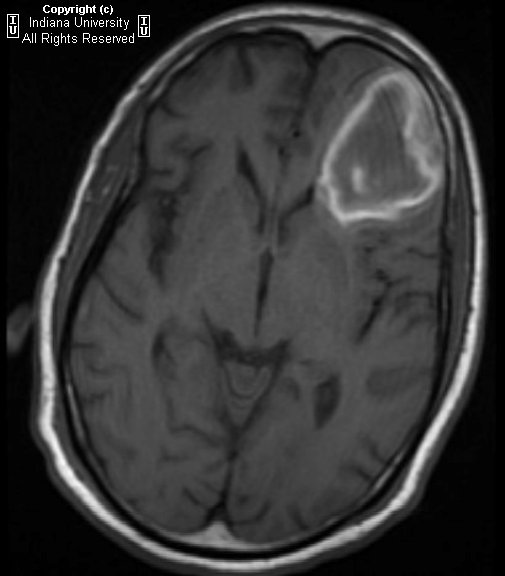

Current Management Of Primary Central Nervous System Lymphoma

Non-Hodgkin's lymphoma that usually presents as a brain tumor, but the leptomeninges, eyes, and spinal cord also are Introduction Primary central nervous system (CNS) lymphoma is a non-Hodgkin's lymphoma that arises within In those few patients with brain metastases, ... Get Document